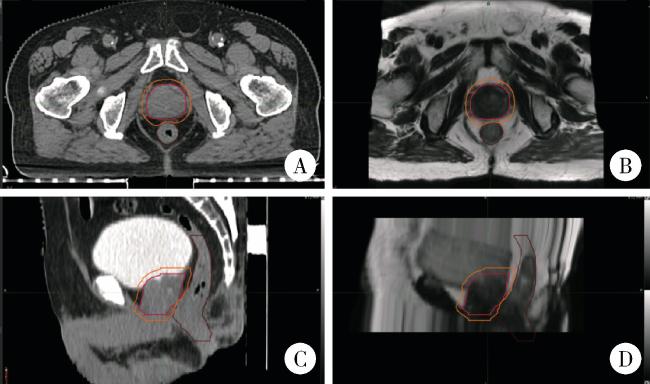

所有患者均采用每日CBCT图像引导放射治疗技术,在放射治疗前采集CBCT图像,选取感兴趣区与定位CT图像进行配准,配准首先通过骨性结构进行自动配准,然后由医生和技师根据靶区位置进行手动微调,调整时参考前列腺、直肠和膀胱的解剖关系,重点关注前列腺区域的匹配,避免直肠前壁误入靶区(图 3)。最终摆位误差结果由系统计算,包含患者实际摆位与治疗计划中心位置在左右(X轴)、头脚(Y轴)、前后(Z轴)方向上的位移误差绝对值。记录摆位误差并比较两组的误差绝对值,以评估摆位精度。

图3 前列腺癌放射治疗患者的CBCT匹配图像

Figure 3 Cone-beam computed tomography(CBCT)-matched images of patients receiving radiotherapy treatment for prostate cancer

A, axial matching images of the CBCT for the patient; B, sagittal matched images of the CBCT for the patients.